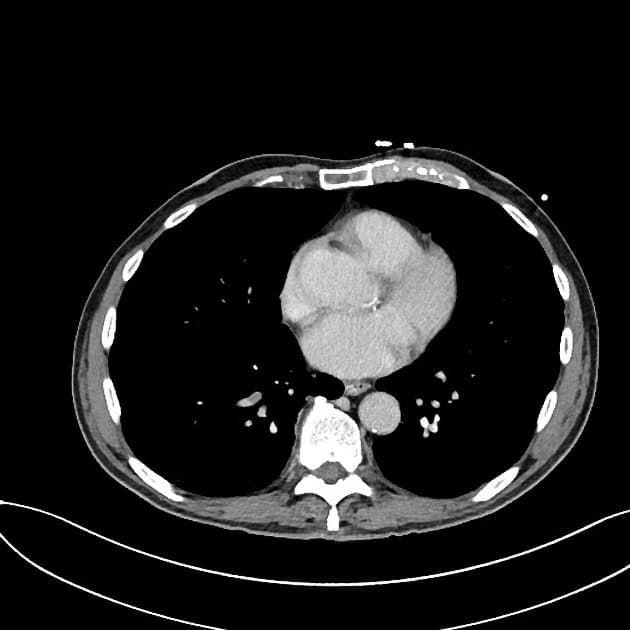

- Dày thành không đối xứng do xâm lấn bởi khối u ở đoạn hai và đoạn ba tá tràng, với sự xâm lấn vào đầu tụy kề bên và gây hẹp lòng tá tràng (duodenal luminal narrowing). Khối u chèn ép tĩnh mạch chủ dưới (IVC) và đẩy lệch các mạch máu mạc treo (mesenteric vessels), nhưng không có xâm lấn hay bao quanh mạch. Ống tụy (pancreatic duct) không giãn.

- Một vài hạch bạch huyết (lymph node) nổi bật thấy ở vùng lân cận khối u.